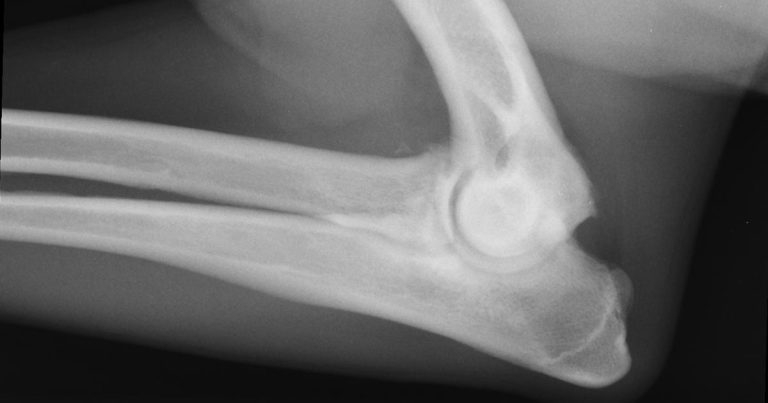

Radiography is useful for confirming presence of OA. It may give an indication as to the severity of the whole pathological picture. However, it is a poor correlator with the clinical picture, prompting the maxim: “Always treat the animal, not the radiograph.” By the time radiographic changes to the bones are present, significant and irreparable damage to the articular cartilage will have occurred (Figure 2).